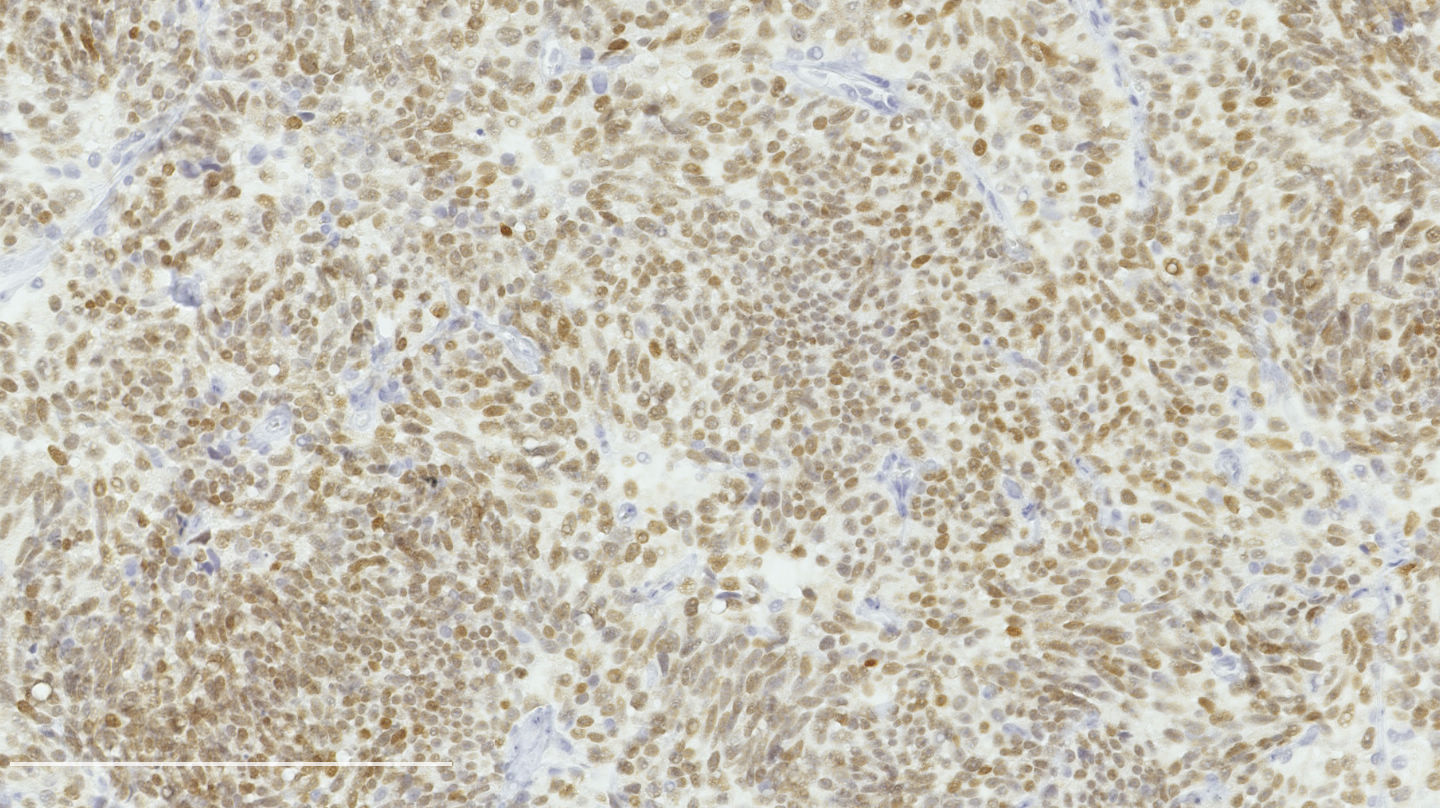

Contributed by Philippe Joubert, M.D., Ph.D.

Positive stains

- Chromogranin, synaptophysin, CD56: diffusely and strongly positive; can be negative in a small number of atypical carcinoids (Hum Pathol 2000;31:1255)

- Ki67: should not be used as a diagnostic criterion (J Thorac Oncol 2019;14:377)

- Mostly useful to differentiate lung carcinoids from high grade neuroendocrine carcinomas, in particular in small biopsies or cytology samples (Arch Pathol Lab Med 2018;142:947, J Thorac Oncol 2014;9:273)

- Usually < 20% but a > 30% cutoff has been proposed (Virchows Arch 2017;470:153, J Thorac Oncol 2014;9:273)

- Reported to be higher than typical carcinoid (2 - 5% versus 9 - 18%) but not proven to be a reliable marker

- A patient undergoes a lobectomy for a well circumscribed nodule. On H&E slide, the tumor exhibits a well differentiated neuroendocrine morphology and you observe the histologic features presented in the image. Which of the following statements is true?

- A Ki67 proliferation rate of > 10% is diagnostic

- It is defined as a well differentiated neuroendocrine tumor with 2 - 10 mitoses per 2 mm² or foci of necrosis

- It is defined as a well differentiated neuroendocrine tumor with 2 - 10 mitoses in 1 high power field or foci of necrosis

- This diagnosis can be made with certainty on small samples (biopsies and cytology)

Practice answer #1

B. It is defined as a well differentiated neuroendocrine tumor with 2 - 10 mitoses per 2 mm² or foci of necrosis. The picture shows a carcinoid lung tumor with a classical neuroendocrine morphology and 2 mitoses in 1 high power field. Even though the whole tumor is not presented here, the presence of 2 mitoses is sufficient for an atypical carcinoid diagnosis.

While Ki67 proliferation rate is frequently > 10% in atypical carcinoids, this feature is not part of the diagnosis (A). C is nearly exact but mitotic count is not made on 1 high power field. Finally, the diagnosis can be suggested on small samples but a thorough examination of a resection specimen is necessary to confirm an atypical carcinoid diagnosis (D).